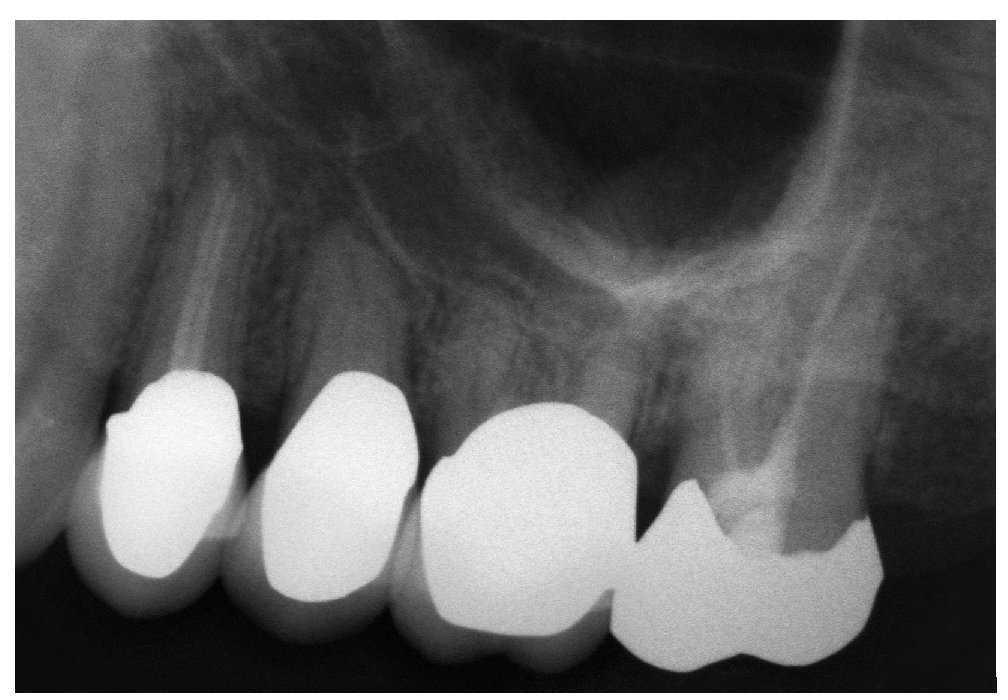

Caso 636, mujer, 61 años

Osteólisis apicales en el diente 27

La paciente acudió a la clínica para el estudio de un dolor en la zona de la apófisis alveolar izquierda del maxilar. En la exploración física destacó la presencia de dolor a la palpación en palatino de los dientes 26 y 27. En la radiografía panorámica practicada se observó una obturación radicular parcial del diente 27 y se identificaron imágenes radiolúcidas en los dos ápices vestibulares del diente 26 (fig. 1). La radiografía intraoral de esta región no aportó información adicional sobre la envergadura de las alteraciones apicales (fig. 2), que sí se apreciaron en la tomografía volumétrica digital (TVD) realizada posteriormente (figs. 3 a 5). Además de una osteólisis extensa con origen en ambos ápices vestibulares del diente 27, se aprecia también la presencia de material de obturación extruido en el ápice radicular palatino del mismo diente. En el mismo lugar se observa también una osteólisis apical. Además, en la porción adyacente del receso alveolar del seno maxilar izquierdo se observan engrosamientos almohadillados de la mucosa que sugieren una sinusitis maxilar crónica. Es posible que las osteólisis apicales sean el factor causal de esta infección lo que, sin embargo, no se ha conseguido demostrar con la TVD.

Figura 1. Radiografía panorámica.